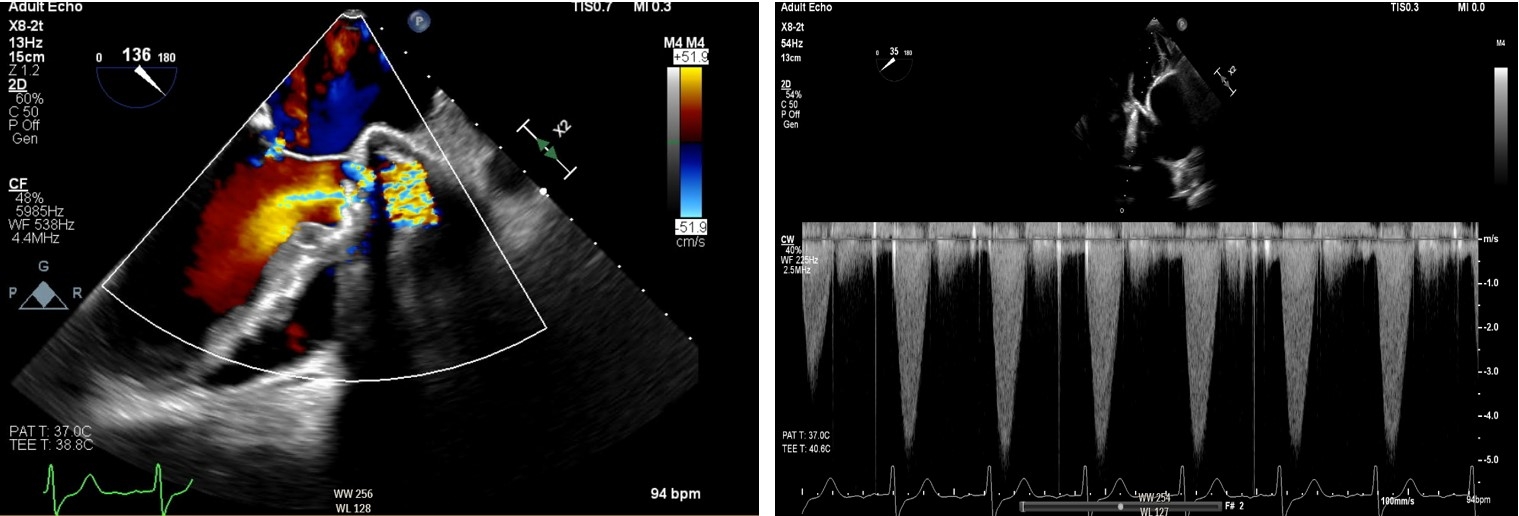

Transthoracic echocardiography (TTE) revealed a peak gradient of 3.7 m/s and mean gradient of 28 mmHg across the prosthetic valve. Urgent transesophageal echocardiography (TEE) showed severely restricted leaflet motion with torrential aortic regurgitation—highly suggestive of valve thrombosis. Due to prohibitive surgical risk, thrombolysis with alteplase (25 mg over 6 hours) was administered. Repeat TEE demonstrated improved leaflet motion (velocity 2.2 m/s, mean gradient 17.6 mmHg), LVEF of 25%, and new severe mitral regurgitation. He was stabilized on milrinone and extubated by hospital day five.